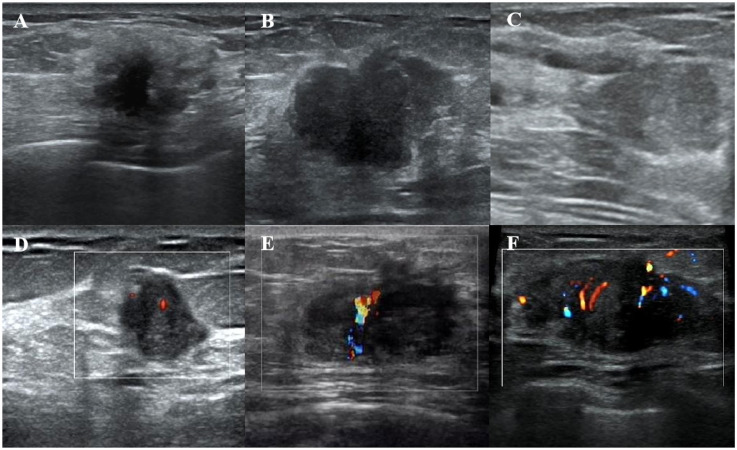

IntroductionTumor-infiltrating lymphocytes (TILs) are key indicators of immune response and prognosis in breast cancer (BC). Accurate prediction of TIL levels is essential for guiding personalized treatment strategies. This study aimed to develop and evaluate machine learning models using ultrasound-derived radiomics and clinical features to predict TIL levels in BC.MethodsThis retrospective study included 256 BC patients between January 2019 and August 2023, who were randomly divided into training (n = 179) and test (n = 77) cohorts. Radiomics features were extracted from the intratumor and peritumor regions in ultrasound images. Feature selection was performed using the "Boruta" package in R to iteratively remove non-significant features. Extra Trees Classifier was used to construct radiomics and clinical models. A combined radiomics-clinical (R-C) model was also developed. Model performance was evaluated using the area under the receiver operating characteristic curve (AUC), accuracy, sensitivity, specificity, and decision curve analysis (DCA) to assess clinical utility. A nomogram was created based on the best-performing model.ResultsA total of 1712 radiomics features were extracted from the intratumor and peritumor regions. The Boruta method selected five key features (four from the peritumor and one from the intratumor) for model construction. Clinical features, including immunohistochemistry, tumor size, shape, and echo characteristics, showed significant differences between high (≥10%) and low (<10%) TIL groups. Both the R-C and radiomics models outperformed the clinical model in the test cohort (area under the curve values of 0.869/0.838 vs 0.627, P < .05). Calibration curves and Brier scores demonstrated superior accuracy and calibration for the R-C and radiomics models. DCA revealed the highest net benefit of the R-C model at intermediate threshold probabilities.ConclusionUltrasound-derived radiomics effectively predicts TIL levels in BC, providing valuable insights for personalized treatment and surveillance strategies.

Abstract Image